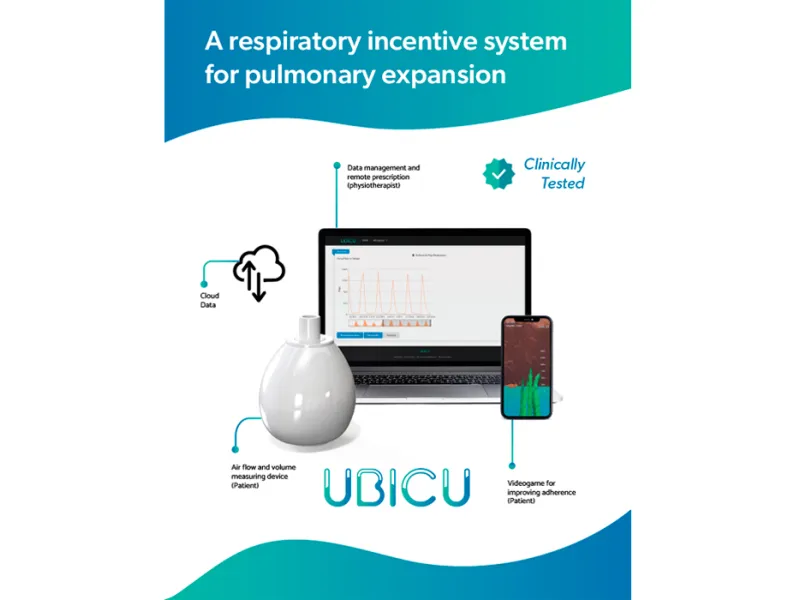

Fue así como se materializó la idea de Ubicu, un incentivo para la re-expansión de los pulmones, un producto tecnológico que brinda apoyo en fisioterapia respiratoria y que determina flujo y volumen de inspiración del aire a partir de unas terapias prescritas al paciente. Cabe anotar que dicho equipo puede usarse para la recuperación de pacientes que padecen otras patologías respiratorias además del SARS-CoV-2.

De acuerdo con el doctor Aguilar, apoyados con Ubicu “los fisioterapeutas y los médicos pueden hacer el seguimiento y conocer la evolución del tratamiento del paciente al obtener datos cuantitativos de su capacidad pulmonar a lo largo de la fisioterapia; también les permite contar con la herramienta necesaria para prescribir la fisioterapia de re-expansión en más de un paciente al mismo tiempo, incluso usar la telemedicina con personas aisladas por el virus o en zonas alejadas de las ciudades principales del país”.

El dispositivo de medida se complementa con un software que aloja un videojuego para estimular visualmente al paciente de tal manera que este permanezca ‘enganchado’ durante el tratamiento. Mientras la persona avanza en los ejercicios que le prescribe el profesional de salud, el incentivo almacena información cuantitativa relacionadas con los datos de flujo y de volumen que son analizados por el fisioterapeuta quien, a su vez, tomará decisiones que favorezcan al paciente durante su proceso de recuperación. Cabe anotar que el incentivo funciona a través de una aplicación disponible para celulares y tabletas con sistemas Android.

Este innovador proyecto ha constado de dos fases. La primera, financiada por la Javeriana Cali con recursos que alcanzaron los $100 millones de pesos, cuyo objetivo consistía en diseñar un prototipo del sistema y hacer pruebas clínicas con 30 pacientes comparando la propuesta con el sistema mecánico actual. La segunda fase se está ejecutando con recursos del Ministerio de Ciencia, Tecnología e Innovación por $487 millones, destinados al escalamiento de productos para el área de salud que incluye un modelo de negocio para poner el sistema en el mercado. En este punto, el incentivo se probará con pacientes que están en tratamiento médico de re-expansión pulmonar. Para esto se creó una alianza con la empresa Prompack, que se encargará del proceso de transferencia de los datos a la nube.

“En ambas fases del proyecto, el diseño busca favorecer la adherencia del paciente a la fisioterapia, tener información cuantitativa del desempeño del paciente para evaluar su desempeño dentro de la fisioterapia de re-expansión pulmonar y mantener información almacenada de los pacientes que atiende el fisioterapeuta para futuros estudios clínicos con una amplia población evaluada”, explican los investigadores en el documento oficial del proyecto.